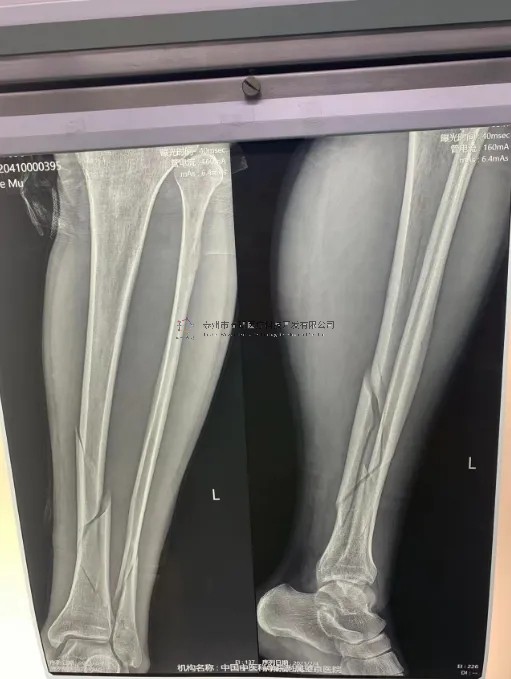

2月份,我们在中国中医科学院望京医院就有多台关于外固定支架的手术,以下介绍一则不开刀CO接骨治疗小腿骨折典型病例:

【所属科室】创一

【基本资料】患者,男,43岁

【患者情况】左胫腓骨近端骨折

【影像图片】